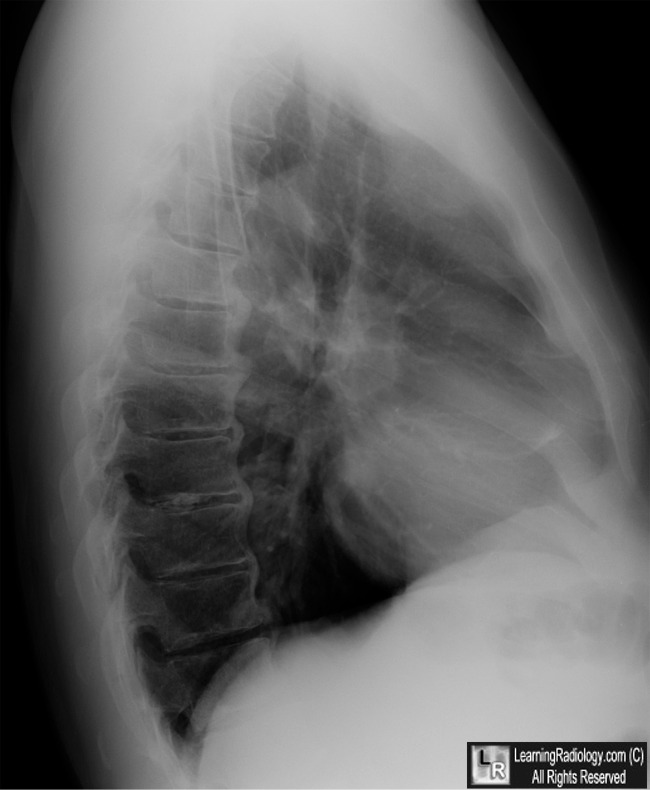

Spondylosis (OA) - Lumbar - Learning - Home

Referred to by many names. Lumbar arthritis . Disc degeneration. Degenerative disc disease ... Access Full Source